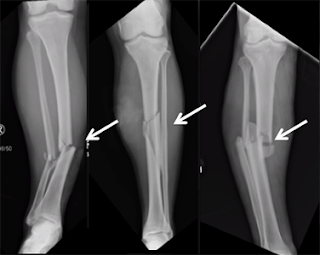

fratura de tibia

Prancha médica com raio-x mostrando ossos quebrados, destacando a gravidade das fraturas.